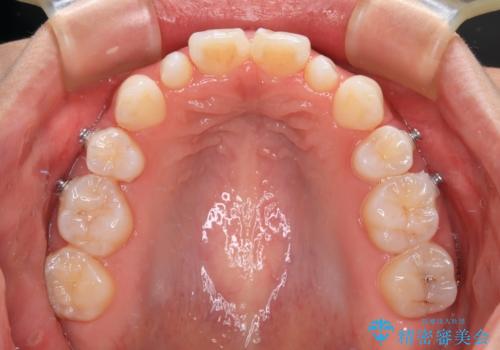

- 矯正装置

- インビザライン

- 3年5ヶ月

上下前歯同士の距離が離れているため、上顎左右第一小臼歯2本を抜歯することで前突を改善することとしました。

しかしながら、左右ともに側切歯が矮小歯であるため、矯正治療で矮小歯前後にスペースを作り、矯正治療後にオールセラミッククラウンにて補綴治療を行うこととしました。